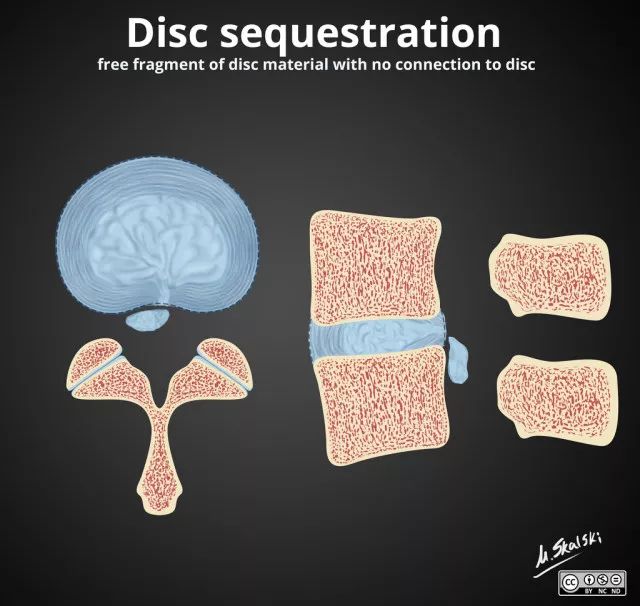

4. 椎间盘游离(Disc Sequestration)

突出髓核与相应椎间盘不连接,可游离到椎管内病变间盘的上或下节段、椎间孔等。

图 6 椎间盘游离,是指髓核完全脱出与椎间盘不连接,游离于椎管内

临床表现

持续性神经根症状或椎管狭窄症状,少数可出现马尾神经综合征,此型常需手术治疗。这是腰椎间盘突出的病理分型之一。